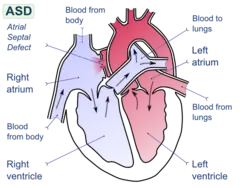

Shunt evaluation

Cardiac shunts can be evaluated through catheterization. Using oxygen as a marker, the oxygen saturation of blood can be sampled at various locations in and around the heart. For example, a left-to-right atrial septal defect will show a marked increase in oxygen saturation in the right atrium, ventricle, and pulmonary artery as compared to the mixed venous oxygen saturation from the oxygenated blood from the lungs mixing into the venous return to the heart. Utilizing the Fick principle, the ratio of blood flow in the lungs (Qp) and system circulations (Qs) can calculate the Qp:Qs ratio. Elevation of the Qp:Qs ratio above 1.5 to 2.0 suggests that there is a hemodynamically significant left-to-right shunt (such that the blood flow through the lungs is 1.5 to 2.0 times more than the systemic circulation). This ratio can be evaluated non-invasively with echocardiography too, however.

A "shunt run" is often done when evaluating for a shunt by taking blood samples from superior vena cava (SVC), inferior vena cava (IVC), right atrium, right ventricle, pulmonary artery, and system arterial. Abrupt increases in oxygen saturation support a left-to-right shunt and lower than normal systemic arterial oxygen saturation supports a right-to-left shunt. Samples from the SVC & IVC are used to calculate mixed venous oxygen saturation.

Balloon septostomy

Catheterization can also be used to perform balloon septostomy, which is the widening of a foramen ovale, patent foramen ovale (PFO), or atrial septal defect (ASD) using a balloon catheter. This can be done in certain congenital heart diseases in which the mechanical shunting is required to sustain life such as in transposition of the great vessels.